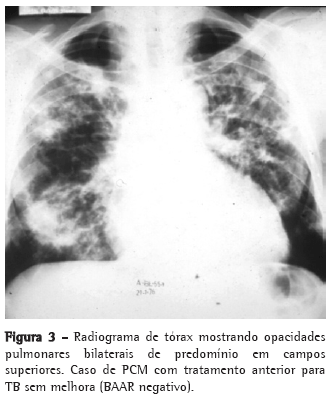

As queixas clínicas, os dados de exame físico e as alterações radiológicas apresentadas por esses doentes, na maioria das vezes, não permitiram a diferenciação segura entre as duas doenças (Figuras 2, 3 e 4).

A PCM acomete muito mais o sexo masculino (15:1), sendo a maioria dos pacientes formada por lavradores ou ex-lavradores com idade entre 30 e 50 anos. Comumente são oligossintomáticos, com poucos achados de exame físico, podendo, no entanto, apresentar exuberantes alterações radiológicas torácicas tanto na radiografia simples quanto na tomografia computadorizada de alta resolução.(11-15)

O acometimento pulmonar é geralmente bilateral, com predomínio nos campos médios e regiões medulares.(16,17)

Por sua vez, a TB acomete ambos os sexos em qualquer idade, com a maioria dos pacientes se apresentando sintomáticos, com exame físico comprometido e alterações radiológicas, em geral, de predomínio em segmentos superiores e posteriores, podendo também ser bilaterais.